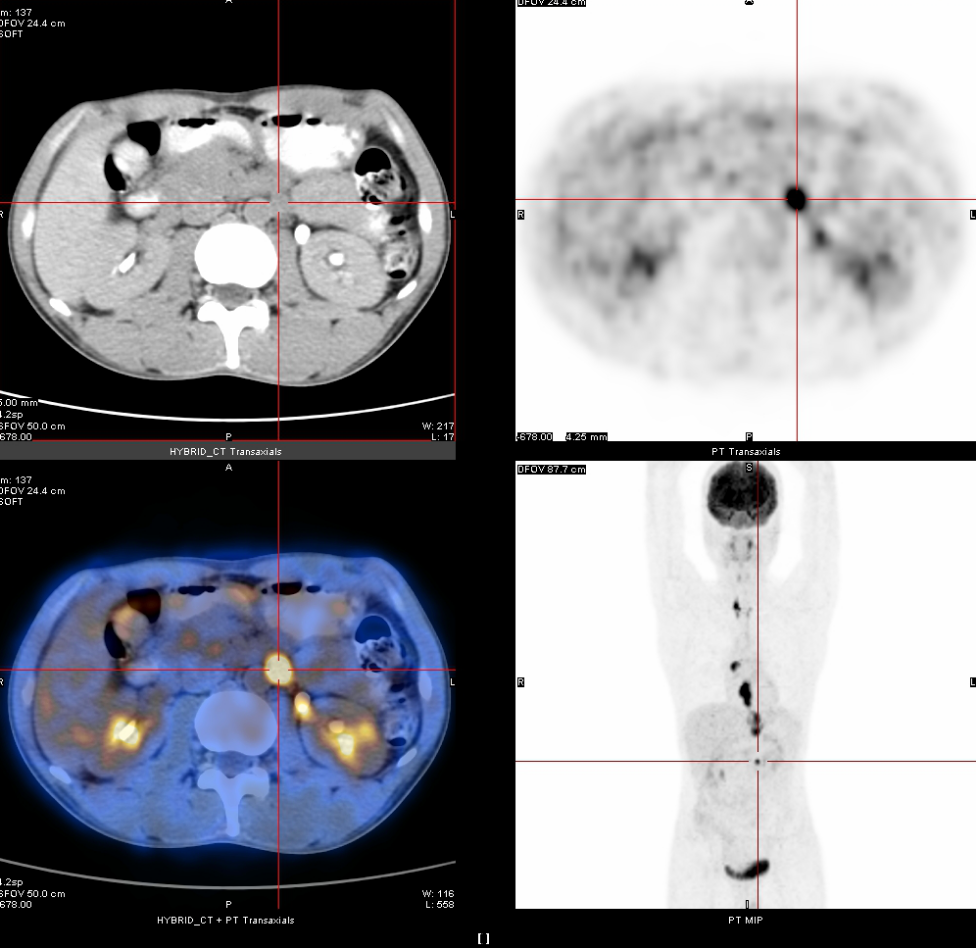

2020年3月13日

全身PET-CT示:1、食管胸中下段管壁不规则增厚,代谢增高,考虑食管癌。2、上纵隔胸廓入口区气管两旁、右下肺静脉后方、贲门区、肝胃间隙、降主动脉后方、膈肌脚后方、腹膜后腹主动脉左旁(左肾门下方平面)见多发高代谢肿大淋巴结,考虑淋巴结转移,建议随访复查。3、右肺上叶前段胸膜下小结节影,代谢未见增高,建议随访复查。4、右肺下叶外基底段条索影,考虑慢性炎性改变。5、双侧上颌窦轻度慢性炎症。6、双侧颈部多发小结节影,代谢未见增高,考虑淋巴结慢性炎性增生。7、肝左叶内侧段小钙化灶。